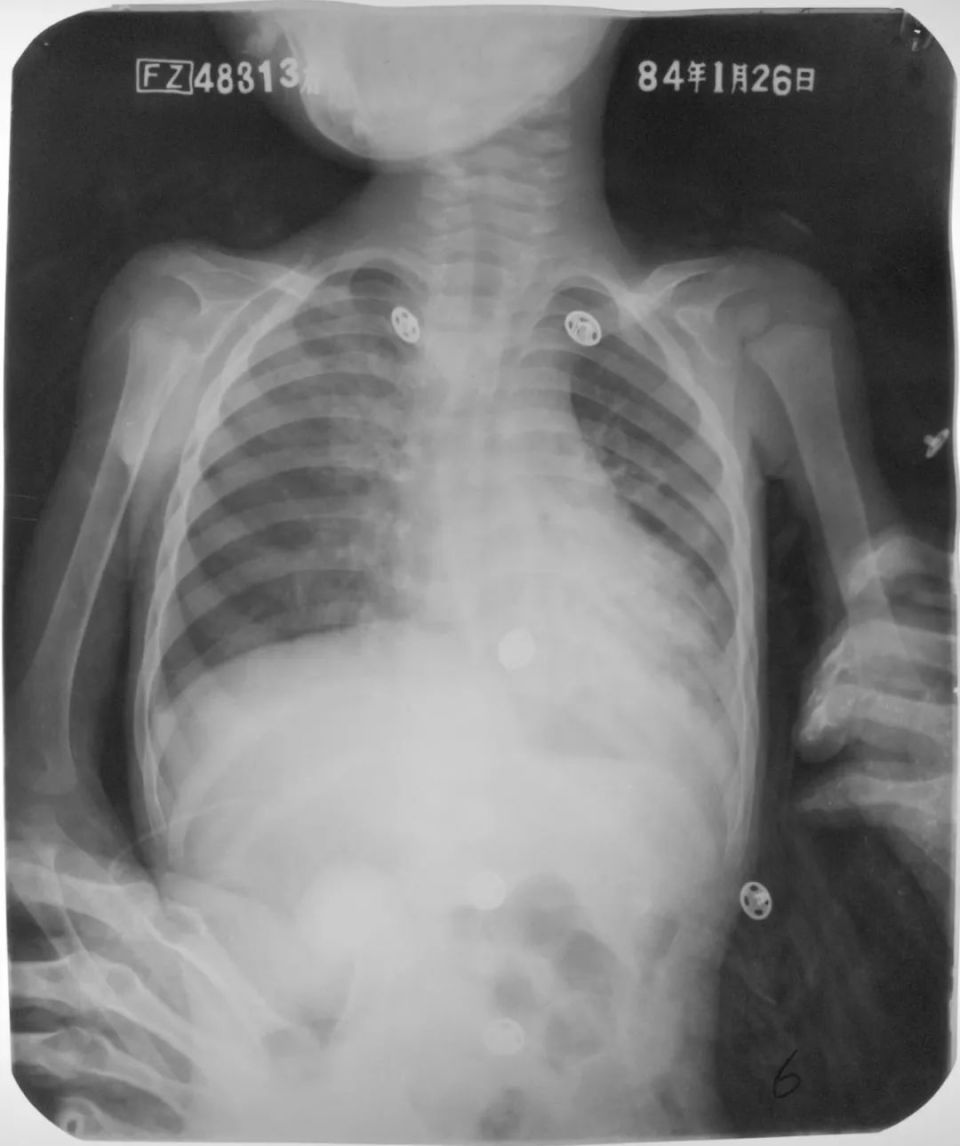

婴幼儿肺炎

图片

胸部正位片示:两肺内带及左肺下野可见不规则的小片状或斑片状边缘模糊的致密阴影,阴影密度不均,局部可见支气管充气征